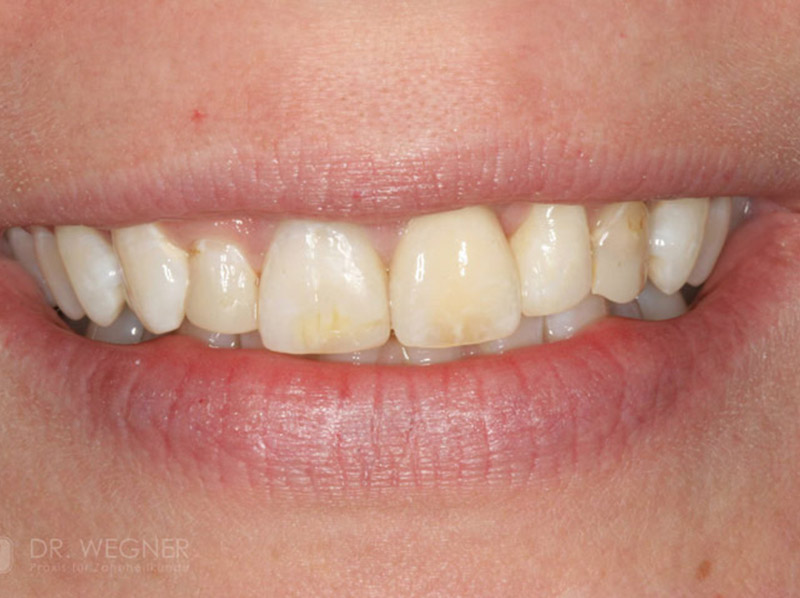

Zahnimplantate werden anhand von moderner virtueller 3D-Planung passgenau geplant und inseriert. Der Vorteil von Implantaten besteht darin, dass festsitzender ästhetischer Zahnersatz auch in solchen Fällen realisiert werden kann, in denen sonst nur herausnehmbare Prothesen möglich wären. Zudem ist im Gegensatz zur Brückenprothetik kein Beschleifen der Nachbarzähne notwendig.

Mittlerweile hat sich die Implantologie zu einem alltäglichen Therapieverfahren mit sehr guten Erfolgsaussichten in der Zahnheilkunde entwickelt. Bei guter Mundhygiene und regelmäßigen Kontrolluntersuchungen können fachmännisch gesetzte Zahnimplantate ein Leben lang halten.